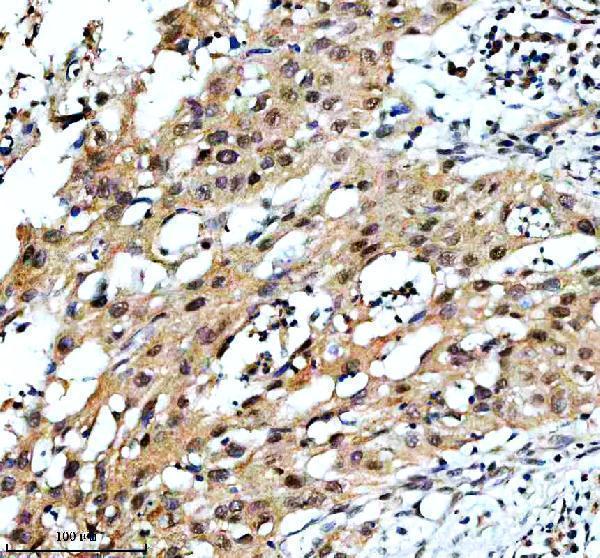

Required in complex with TBPL2 for the differentiation of myoblasts into myocytes. The complicated replaces TFIID at specific promoters at an early stage in the differentiation procedure.

| Gene Name: | TAF3 |